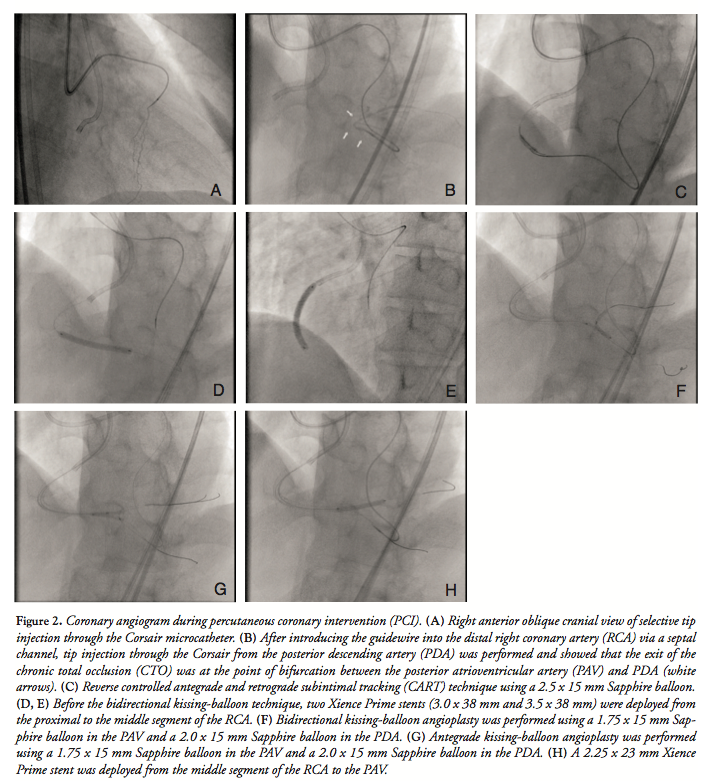

After obtaining informed consent, PCI of the CTO was performed. An 8 Fr AL1 guiding catheter with a side hole (Mach 1; Boston Scientific) was negotiated into the RCA and a 7 Fr VL3.5 guiding catheter with a side hole (Mach 1) was introduced into the left coronary artery. Because the exit of the CTO was bifurcated and the septal channel was well visualized at the time of diagnostic coronary angiography, we initially attempted a retrograde approach. A Fielder FC guidewire (Asahi Intecc) with a Corsair microcatheter (Asahi Intecc) was introduced into the targeted proximal major septal branch. The guidewire was then removed, and selective tip injection through the Corsair was performed to clarify the connection between the septal branch and the PDA (Figure 2A). The channel was well visualized angiographically, and a Sion guidewire (Asahi Intecc) with a Corsair was successfully introduced into the septal channel. After introducing the guidewire into the distal RCA from PDA to PAV, the Corsair was advanced into the PDA. Tip injection through the Corsair from the PDA was performed, which confirmed that the exit of the CTO was at the point of bifurcation between the PAV and PDA (Figure 2B). The guidewire was then exchanged for a Gaia Second (Asahi Intecc) and advanced retrograde into the CTO from the PDA. Because the retrograde wire was not advanced into the proximal true lumen, reverse controlled antegrade and retrograde subintimal tracking (CART) technique was performed with a 2.5 x 15 mm Sapphire balloon (Orbusneich Medical) (Figure 2C). Finally, a Conquest Pro guidewire (Asahi Intecc) was successfully introduced into the proximal true lumen. The retrograde wire was advanced into the antegrade guiding catheter with the Corsair and exchanged for a 330 cm RG3 guidewire (Asahi Intecc). Wire externalization was then completely achieved.

After wire externalization, we tried to navigate a second protection wire into the PAV with a Crusade double-lumen catheter (Kaneka Medix), but were unsuccessful. Reverse-wire technique using a Fielder FC guidewire was attempted antegrade, but was also unsuccessful. To modify the lesion characteristics, we decided to perform bidirectional kissing-balloon angioplasty. Prior to this, because we had to remove the externalized RG3 guidewire, 2 Xience Prime stents (3.0 x 38 mm and 3.5 x 38 mm) (Abbott Vascular) were deployed from the proximal to the middle segment of the RCA (Figures 2D and 2E) while enough support from the externalized RG3 wire was available. Subsequently, a Sion blue guidewire (Asahi Intecc) was advanced antegrade into the PDA with a Crusade. The RG3 guidewire was removed, and a Route guidewire (Asahi Intecc) was advanced retrograde into the PAV from the PDA through the Corsair. A 2.0 x 15 mm Sapphire balloon (Orbusneich Medical) was

advanced into the bifurcation lesion antegrade, and a 1.75 x 15 mm Sapphire balloon (Orbusneich Medical) was advanced retrograde. The bidirectional kissing-balloon technique was then performed (Figure 2F). Following this, we successfully navigated a Balance guidewire (Abbott Vascular) antegrade into the PAV with a Crusade. Subsequently, we performed antegrade kissing-balloon angioplasty with a 2.0 x 15 mm Sapphire balloon in the PDA and a 1.75 x 15 mm Sapphire balloon in the PAV (Figure 2G). A 2.25 x 23 mm Xience Prime stent was deployed from the middle segment of the RCA to the PAV (Figure 2H). Postdilatation was performed with stent balloons, and a final coronary angiogram revealed an excellent result, with preserved flow in both the PAV and PDA (Figure 3). The postprocedure course was uneventful, and no major complications, including severe ischemic events, heart failure, or access-site complications, were observed. The patient was discharged 2 days after the procedure without symptoms.